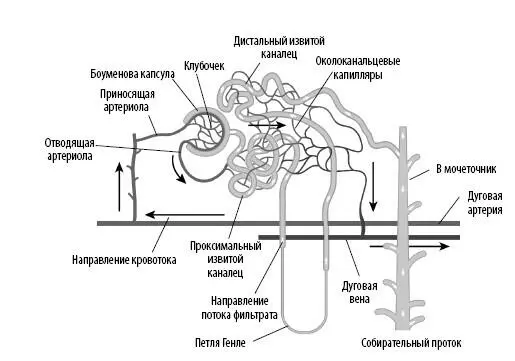

Фильтрация происходит в сферических структурах, называемых почечными тельцами. В них содержится капиллярная сеть — почечные клубочки, которые выходят из приносящих (афферентных) артериол и сворачиваются в чашеобразную структуру — Боуменову капсулу. В почечном тельце создается огромное давление, из-за которого вода и растворенные в крови продукты жизнедеятельности отфильтровываются капиллярами через специальные поры и попадают в Боуменову капсулу — начало почечного канальца.

Почечные клубочки

Эти капиллярные узлы формируют первичный капиллярный слой нефрона (всего их два). Клубочки образуют фильтрующую поверхность с площадью свыше 500 кв. см. Капиллярные стенки клубочков формируют подобие сита, которое пропускает небольшие молекулы (воду, соли, гормоны, глюкозу и водорастворимые витамины) в Боуменову капсулу и блокирует крупные молекулы (белки плазмы (альбумин) и клетки крови). Процеженная кровь выходит из клубочков через отводящие (эфферентные) артериолы, которые разветвляются на вторичное капиллярное русло, околоканальцевые капилляры и прямые сосуды. Далее кровь проходит по петле Генле и попадает в венозную систему.

У корковых нефронов более короткие петли Генле, чем у юкстамедуллярных.

Боуменова капсула сужается, образуя проксимальный извитой каналец. Он окружен околоканальцевыми капиллярами и прямыми сосудами, которые реабсорбируют воду, питательные вещества и минералы из фильтрата в кровь. Эпителиальные клетки, выстилающие канальцы, содержат микроворсинки, которые увеличивают рабочую поверхность и повышают эффективность реабсорбции. Также в этих клетках присутствует много митохондрий — источников энергии, необходимой для транспортировки растворенных веществ против градиента концентрации.

При повороте вниз каналец образует нисходящее колено петли Генле. Здесь происходит активная реабсорбция воды в кровь, поскольку проницаемость канальца изменяется только для воды. Затем восходящее колено петли Генле переходит в менее активный дистальный извитой каналец, который попадает в собирательный проток.

Собирательные протоки

Собирательные протоки не являются частью нефрона; они собирают фильтрат из нескольких нефронов и определяют концентрацию мочи. Регулирует этот процесс гипофизарный антидиуретический гормон (АДГ), который увеличивает проницаемость стенок для воды и позволяет большему ее количеству реабсорбироваться в кровь. Этим и объясняется тот факт, что наша моча по утрам более концентрирована: в ночное время выделяется больше АДГ. Фильтрат (а теперь это уже моча) перетекает из собирательных протоков в почечные чашки, затем в почечную лоханку и выводится в мочеточник.